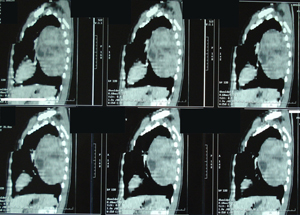

Αξονική τομογραφία θώρακος. Διακρίνεται η παρουσία μάζας από μαλακά μόρια προπερικαρδιακά, οπισθοστερνικά, με προβολή προς τα αριστερά. Η μάζα αυτή έχει ομαλά όρια με ομοιογενή πυκνότητα. Οι συχνότεροι όγκοι που εντοπίζονται σε αυτή την θέση είναι του θύμου αδένα.

Εικόνα 4

Αξονική τομογραφία θώρακος του ίδιου ασθενούς σε διαφορετικό επίπεδο.